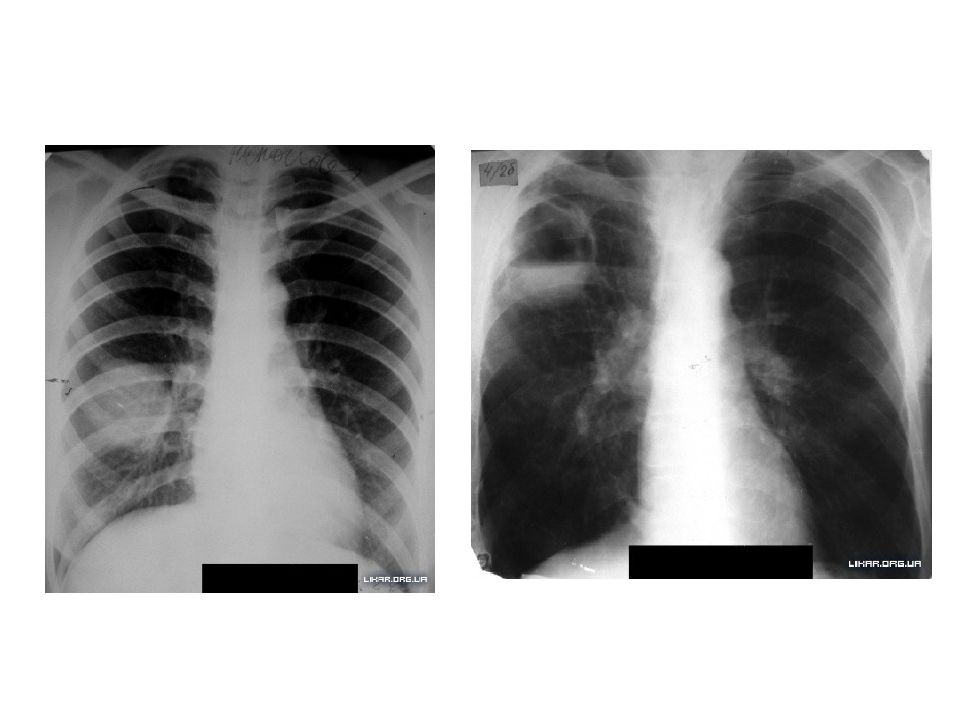

Медицинская тема: легочные осложнения при пневмонии